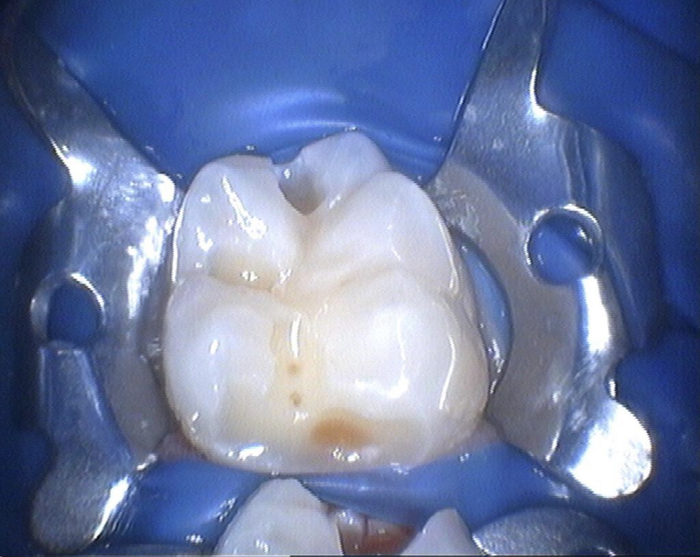

Снимки

Это собственно зуб под удаление молочный

А это тот самый сложный кариес. Как сказала врач БЕЛЫЙ КАРИЕС который очень сложно лечить